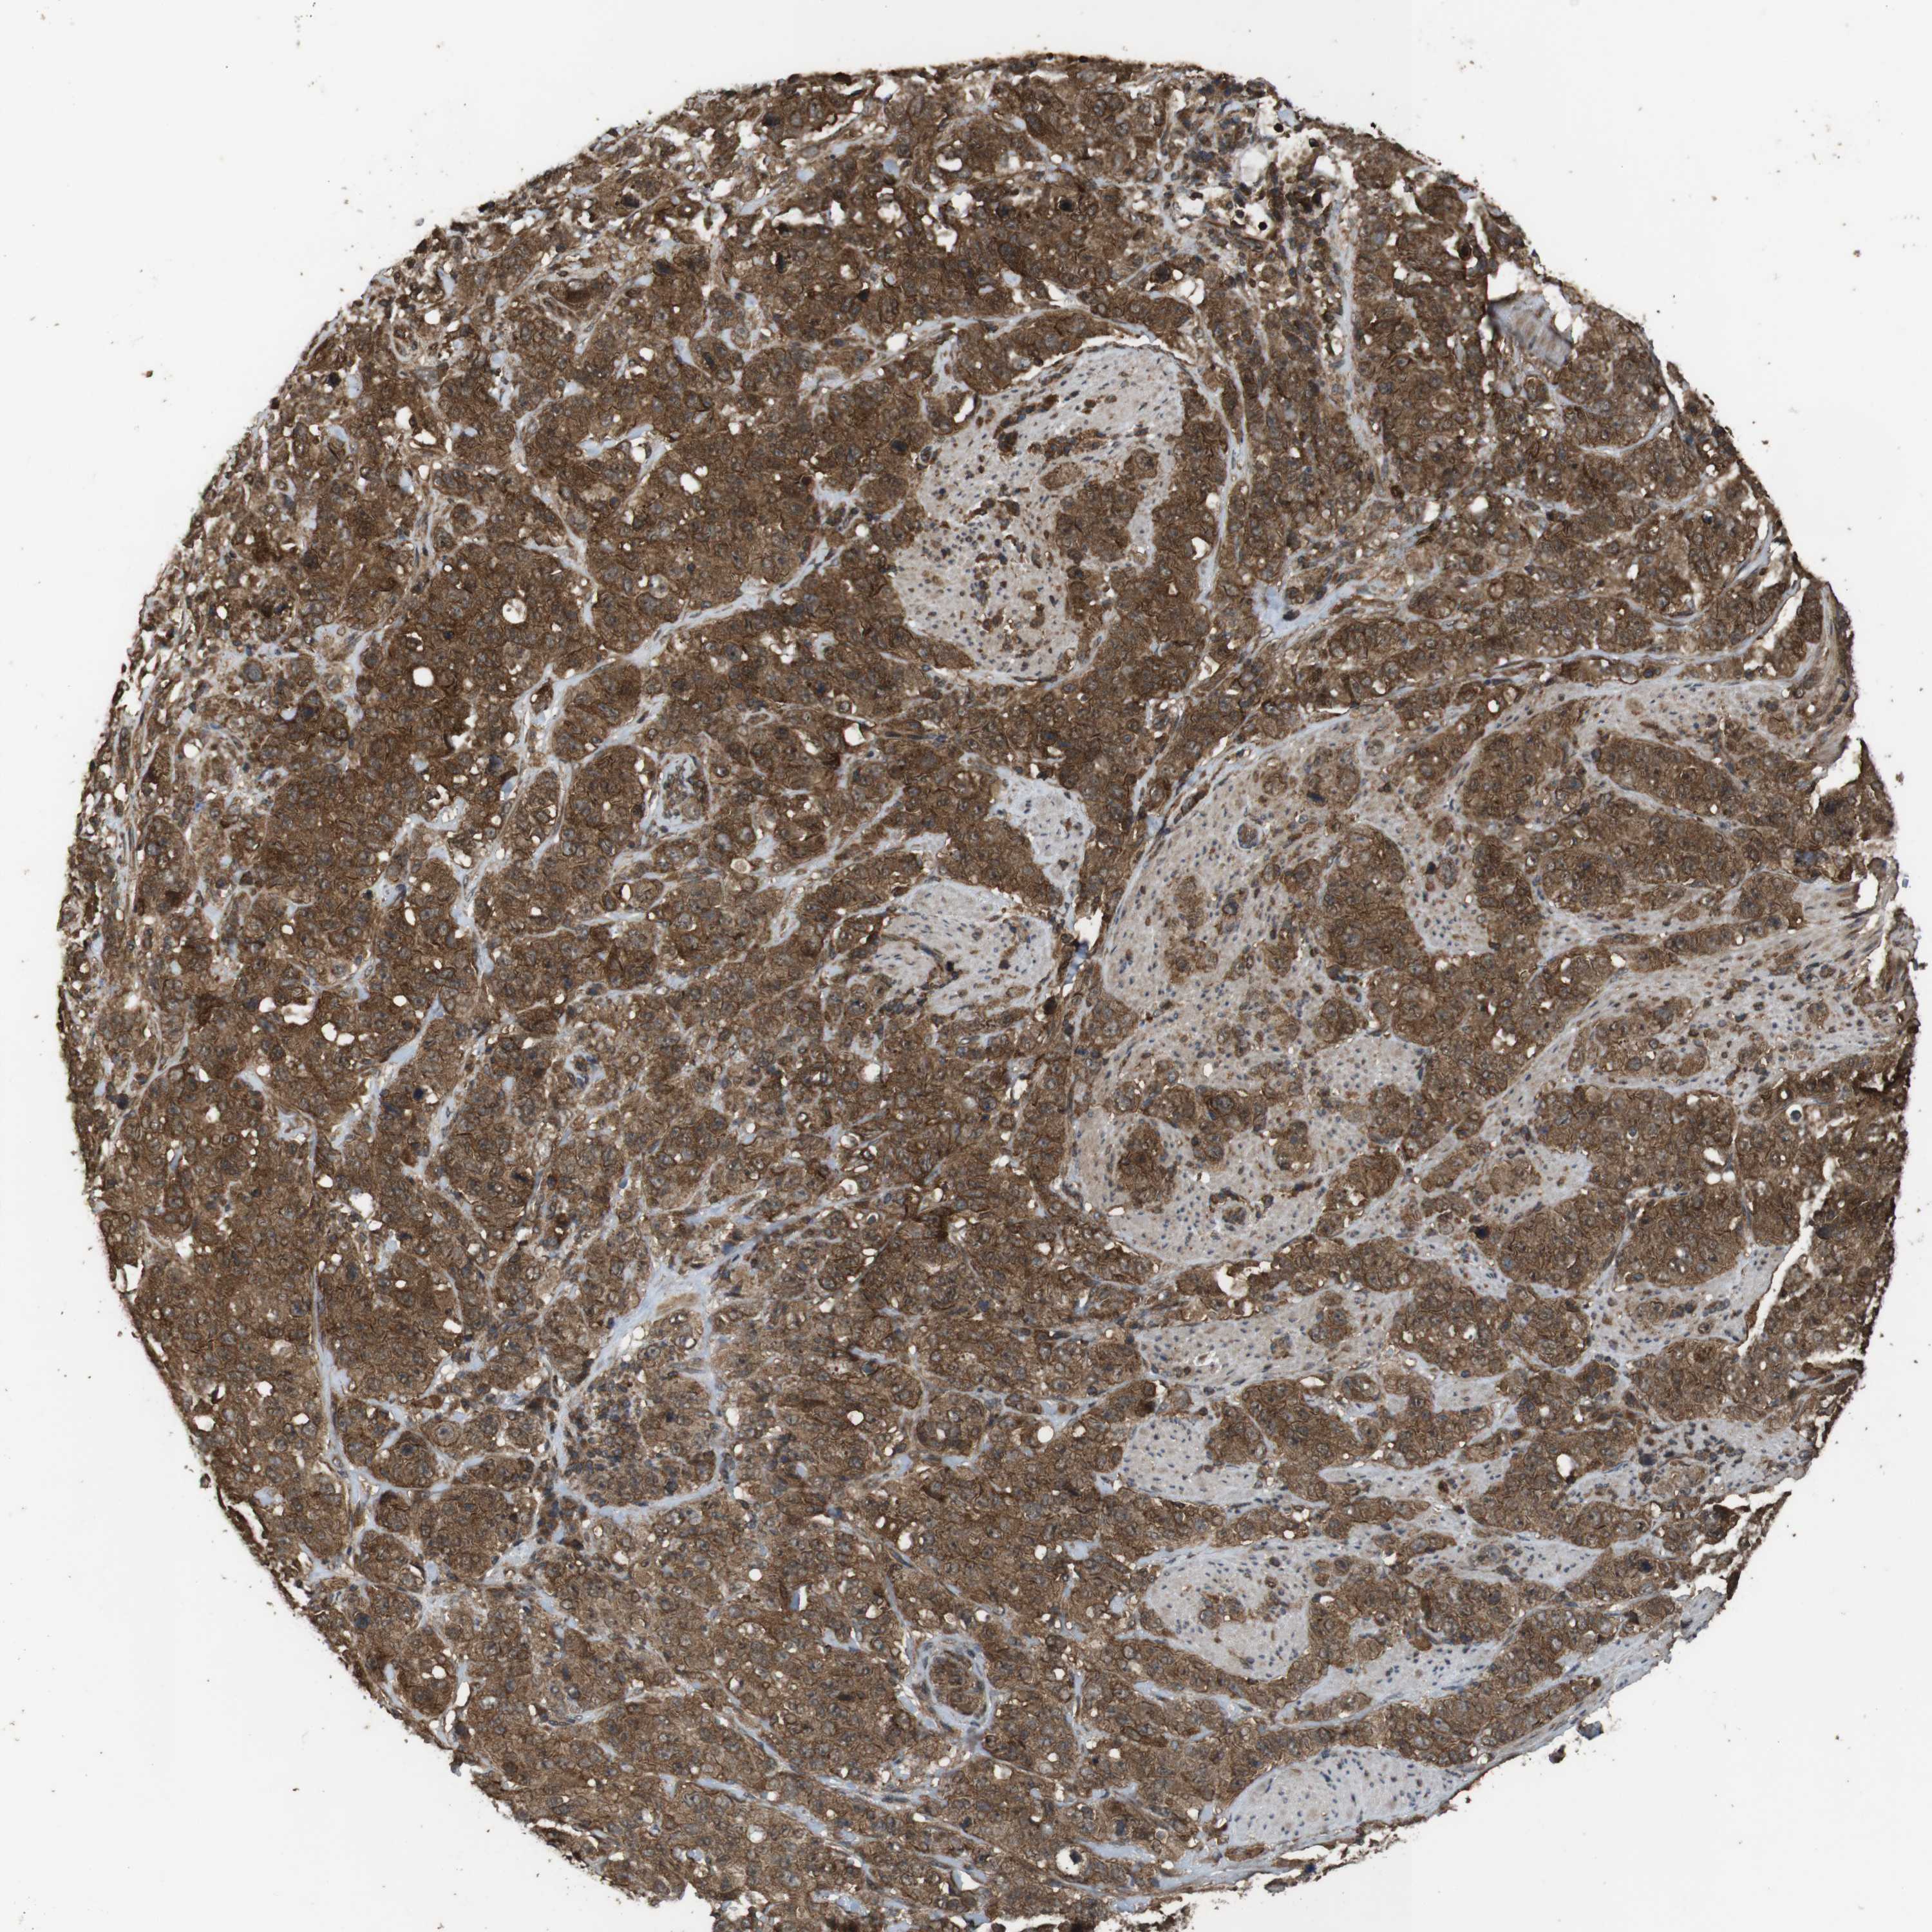

STOMACH CANCER - Protein expressioni

A mouse-over function shows sample information and annotation data. Click on an image to view it in a full screen mode. Samples can be filtered based on level of antibody staining by selecting one or several of the following categories: high, medium, low and not detected. The assay and annotation is described here.

Note that samples used for immunohistochemistry by the Human Protein Atlas do not correspond to samples in the TCGA dataset.

Antibody stainingi

Antibody staining in the annotated cell types in the current human tissue is reported as not detected, low, medium, or high, based on conventional immunohistochemistry profiling in selected tissues. This score is based on the combination of the staining intensity and fraction of stained cells.

Each image is clickable and will lead to virtual microscopy that enables deeper exploration of all samples and also displays staining intensity scores, fraction scores and subcellular localization as well as patient and tissue information for each sample.

Antibody HPA018951

Antibody CAB013716

Staining

High

Medium

Low

Not detected

Intensity

Strong

Moderate

Weak

Negative

Quantity

>75%

75%-25%

<25%

None

Location

Nuclear

Cytoplasmic/membranous

Cytoplasmic/membranous,nuclear

Adenocarcinoma, NOS

Adenocarcinoma, High grade